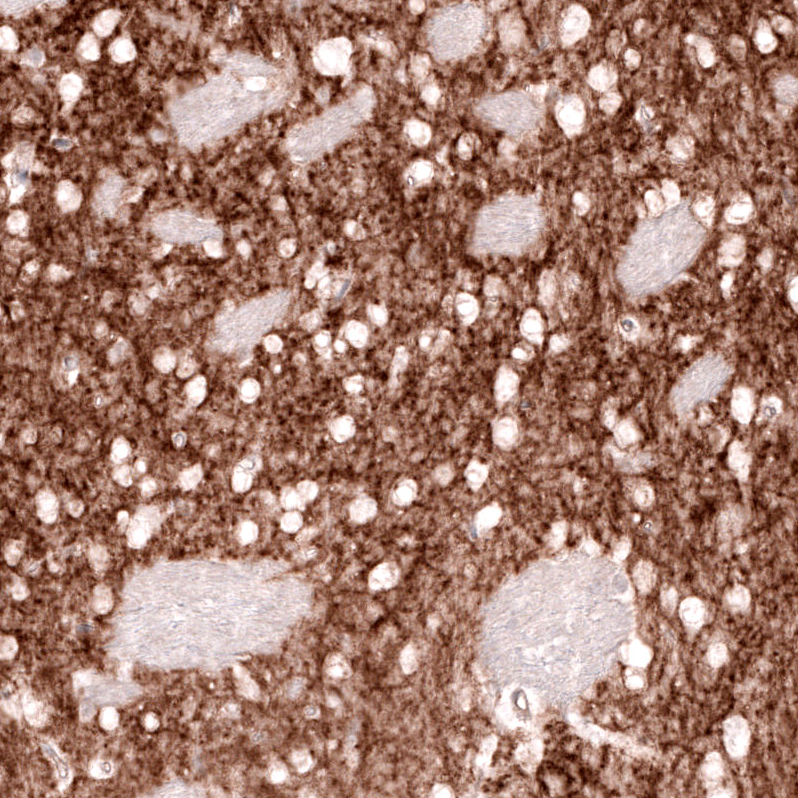

Immunohistochemical staining of rat caudate nucleus shows moderate to strong positivity in neuronal processes.